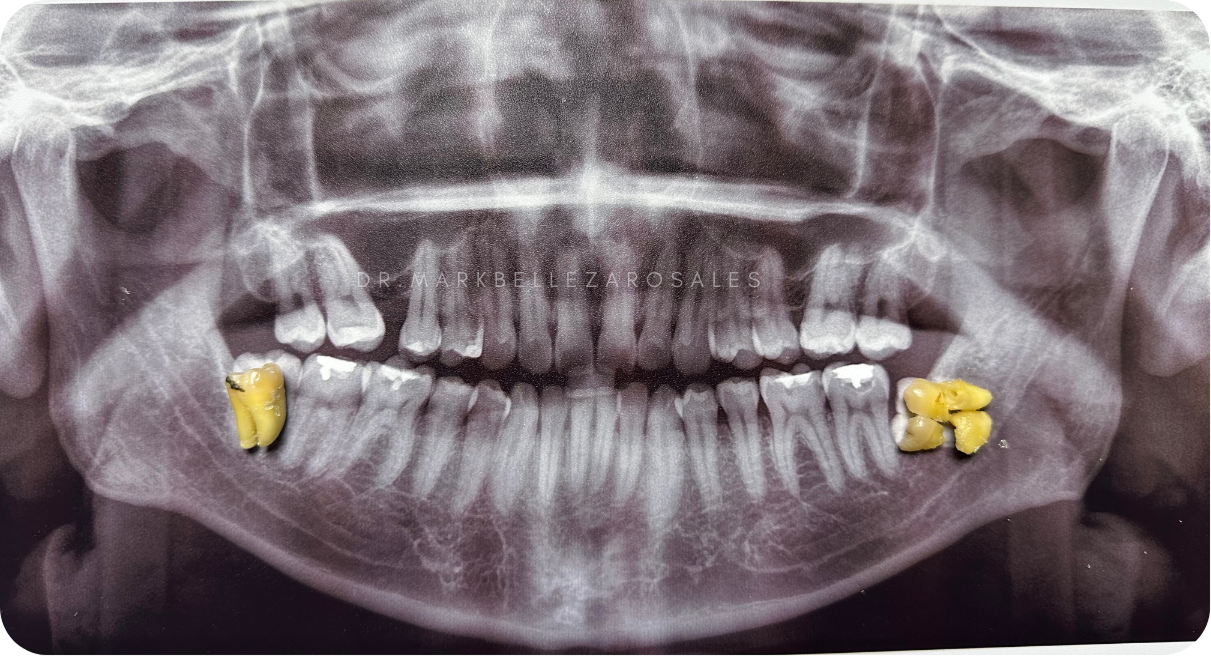

Wisdom tooth removal is a dental procedure performed to extract one or more third molars that may be impacted, painful, or causing crowding and infection. The procedure helps prevent future dental problems and relieves discomfort while protecting overall oral health.